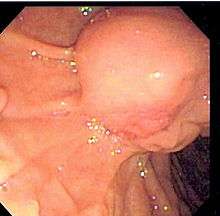

Common bile duct stone, also known as choledocholithiasis, is the presence of gallstones in the common bile duct (thus choledocho- + lithiasis). This condition causes jaundice and liver cell damage, and requires treatment by cholecystectomy and/or ERCP.

Choledocholithiasis (stones in common bile duct) is one of the complications of cholelithiasis (gallstones), so the initial step is to confirm the diagnosis of cholelithiasis. Patients with cholelithiasis typically present with pain in the right-upper quadrant of the abdomen with the associated symptoms of nausea and vomiting, especially after a fatty meal. The physician can confirm the diagnosis of cholelithiasis with an abdominal ultrasound that shows the ultrasonic shadows of the stones in the gallbladder.

The diagnosis of choledocholithiasis is suggested when the liver function blood test shows an elevation in bilirubin and serum transaminases. Other indicators include raised indicators of ampulla of vater (pancreatic duct obstruction) such as lipases and amylases. In prolonged cases the INR may change due to a decrease in vitamin K absorption. (It is the decreased bile flow which reduces fat breakdown and therefore absorption of fat soluble vitamins). The diagnosis is confirmed with either an MRCP (magnetic resonance cholangiopancreatography), an ERCP, or an intraoperative cholangiogram. If the patient must have the gallbladder removed for gallstones, the surgeon may choose to proceed with the surgery, and obtain a cholangiogram during the surgery. If the cholangiogram shows a stone in the bile duct, the surgeon may attempt to treat the problem by flushing the stone into the intestine or retrieve the stone back through the cystic duct.

On a different pathway, the physician may choose to proceed with ERCP before surgery. The benefit of ERCP is that it can be utilized not just to diagnose, but also to treat the problem. During ERCP the endoscopist may surgically widen the opening into the bile duct and remove the stone through that opening. ERCP, however, is an invasive procedure and has its own potential complications. Thus, if the suspicion is low, the physician may choose to confirm the diagnosis with MRCP, a non-invasive imaging technique, before proceeding with ERCP or surgery.